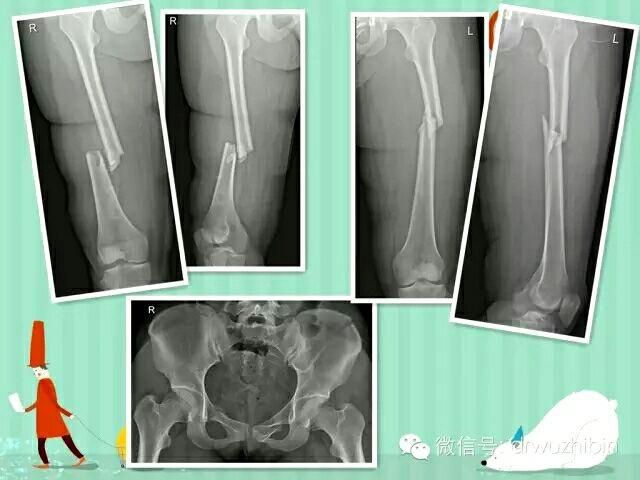

以下是近期收治的一名骨盆多發性骨折合并泌尿系損傷、雙側股骨幹骨折的患者,術後康複良好。